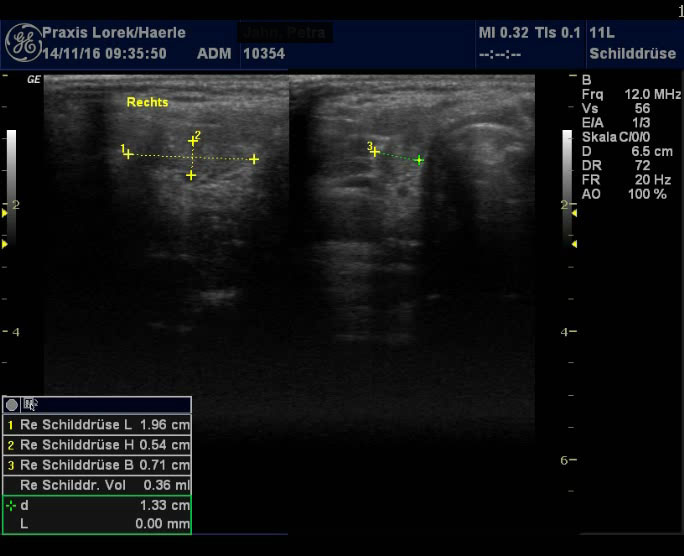

Abb. 1 und 2: Kleine

Rest-Schilddrüse bds. nach subtotaler Thyreoidektomie 1995 wegen Morbus

Basedow. Restgewebe postoperativ geringfügig gewachsen, typisches

inhomogenes Muster wie bei einer Basedow-Struma. Patientin mit

polyglandulärem Syndrom: Diabetes mellitus Typ I, Endokrine Ophthalmopathie,

Vaskulitis mit Fingerendgliedamputationen.